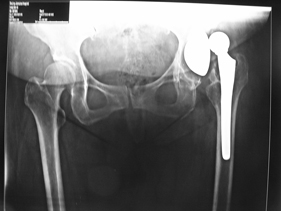

rivision total hip replacement for dislocation and severe bone defect

(post-op)rivision total hip replacement for dislocation and severe bone defect

anterior-posterior view of bilateral hips